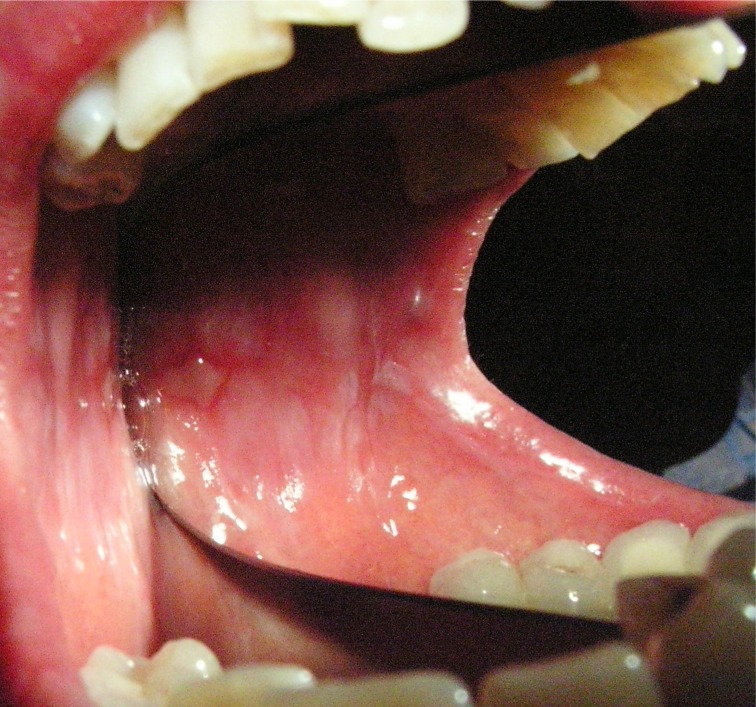

Salve a tutti e ringrazio per le repentine risposte... no, non ho sentito male...ha proprio detto alla mia domanda di cos'è un ispessimento, "è un leucoma di forma cancerosa, che può portare ad un cancro". Primo sono entrata nel panico, secondo mi ha detto "si potrà intervenire "grattando" la gengiva, sempre che ciò non sia già compromesso, intanto, prenda appuntamento per l'igiene e faremo sia le lastrine che un'orto panoramica"... dopo di che il mio cervello è andato in tilt. ora, se vado ogni sei mesi a fare l'igiene, mi lavo accuratamente i denti, passo il filo, etc etc perchè non l'hanno notato prima? ma a questa domanda mi rendo conto, che non possiate rispondere...però io intanto ho prenotato per settimana prox un'orto panoramica. Spazzolo la gengiva "incriminata", anche se fa male, ed evito di masticarci sopra... però permettetemi di farvi un'altra domanda... in cosa consisterà l'intervento qualora ce ne fosse bisogno? è doloroso? il post operatorio? io insegno, e devo essere attiva e attenta... devo seguire i miei ragazzi e se esistesse qualcosa di meno invasivo ne sarei felice. Perdonate la mia ansia e paura, ma capite bene che dopo un'affermazione del genere non sto ragionando: Grazie mille per la disponibilità